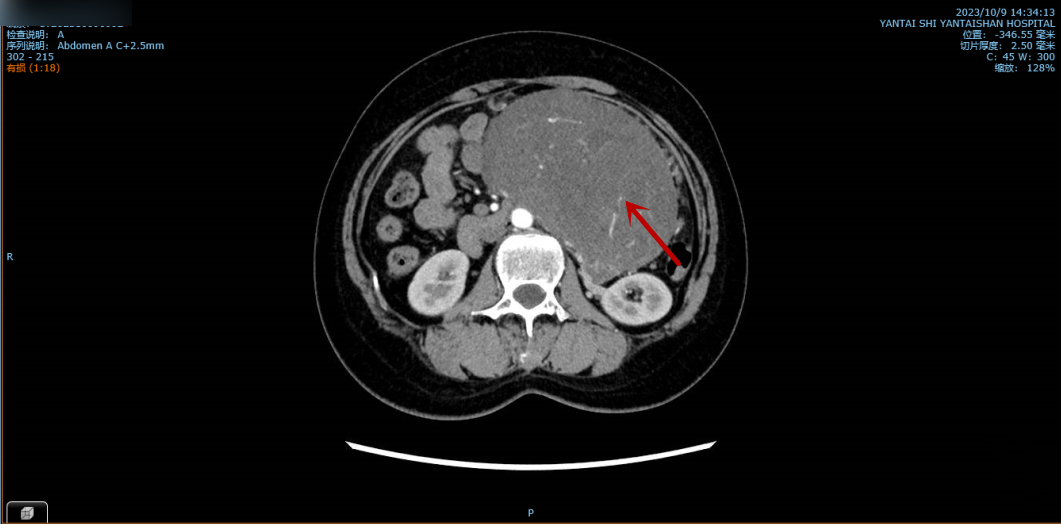

图中所示为巨大腹膜后肿瘤。

这2个月以来,孙女士的腹部日渐隆起,并出现压迫症状,腹痛、腹胀较以前更为严重,稍多进食就会呕吐。住院后的增强CT检查显示:腹膜后巨大肿瘤压迫十二指肠及空肠起始段并导致梗阻,肿瘤和腹主动脉、下腔静脉等大血管关系密切,肿瘤指标明显升高。如此以来,手术难度进一步增加,但患者的腹痛及压迫症状持续加重中,手术迫在眉睫。